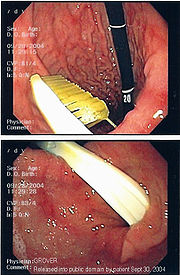

Endoscopic still of gastric foreign body (toothbrush)

Commonly swallowed objects include coins, buttons, batteries, and small bones (such as fish bones), but can include more complex objects, such as eyeglasses, spoons, and toothbrushes (see image).